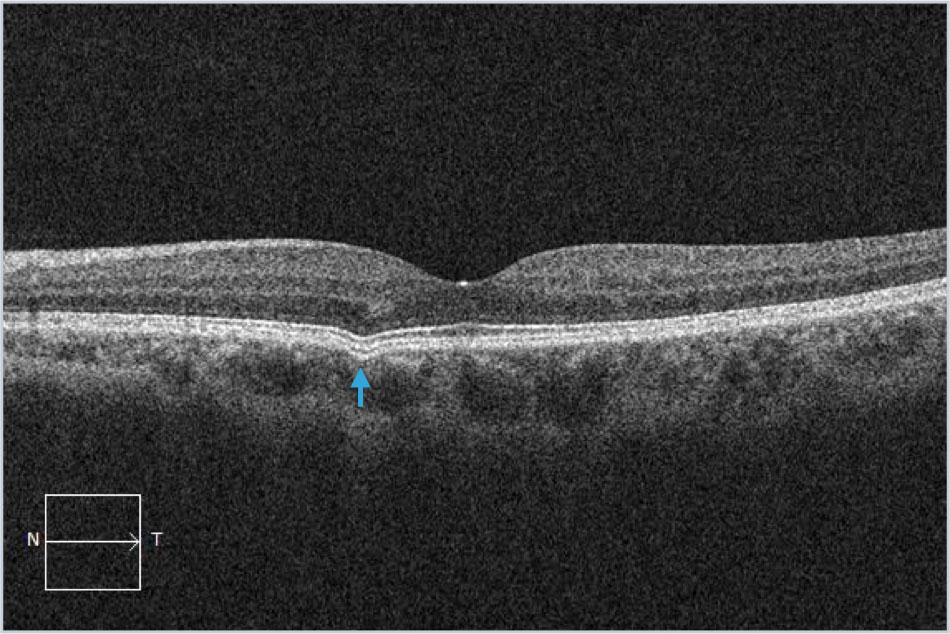

Focal choroidal excavation is commonly abbreviated as FCE and can be noted incidentally as well as in patients with an antecedent history of inflammatory chorioretinal disease.

Examples (blue arrows) from different patients with focal choroidal excavation. This finding is often noted incidentally and patients rarely have symptoms. Occasionally it can be associated with macular neovascularization and inflammatory disorders. The key visual sign on SD-OCT imaging is the outward bowing of the RPE.